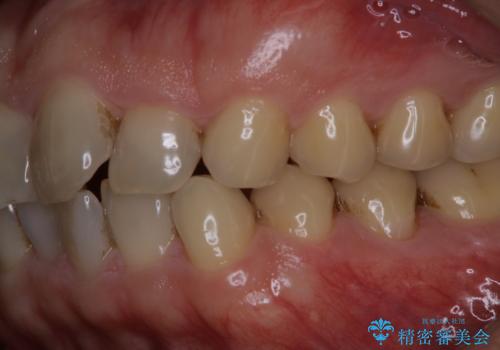

細かいステインをPMTCでOFF

- 歯ブラシをしてもとれないステインが気になるとのことで来院されました。PMTC60分コースを行いました。

PMTCは、歯に付着した汚れを除去していくため、着色が気になる場合にも行うことができます。ご自身でのセルフケアだけで着色を落とそうとすると、逆に歯を傷つけてしまったり、精密に汚れを除去できないこともあります。また、日常生活で着色しやすい飲食物を避けたりすることはストレスに感じてしまったり、あまり現実的ではありません。

毎日丁寧に歯磨きをしていても、日常生活での飲食物などにより着色してしまうことはあります。PMTCでは、歯の表面の凸凹にミネラルを補給して、ツルツルの表面に仕上げます